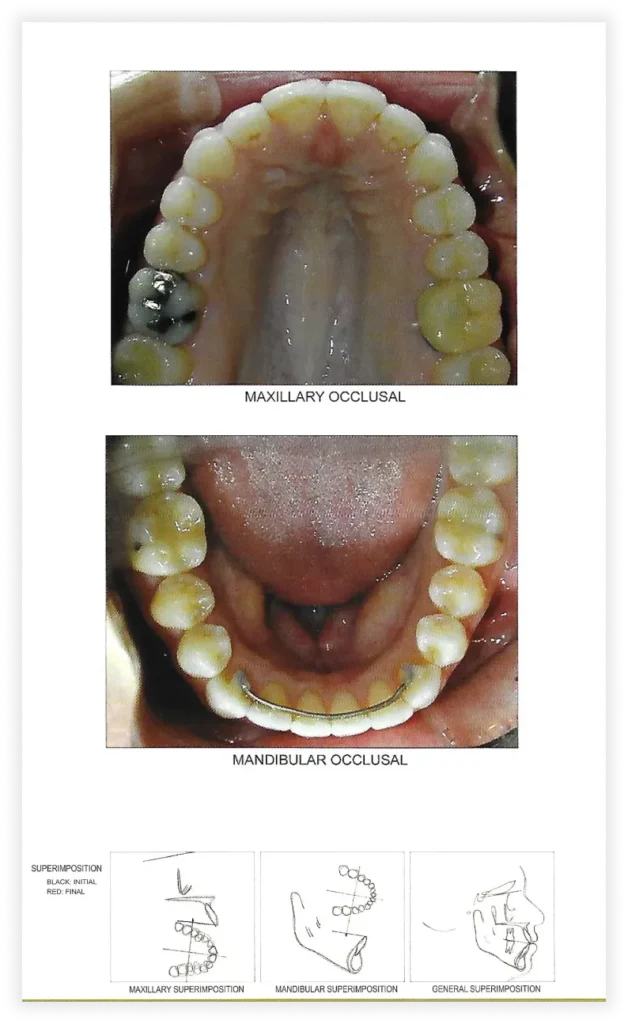

Smile Gallery

Take a look at some of our cases and successful transformations below.

Final Photos